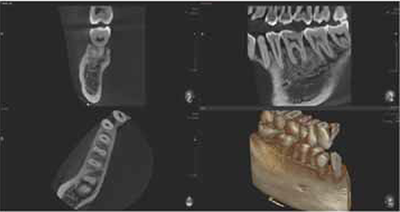

8X5 scans can provide more extended oral information on maxillary or mandibular areas. An accurate treatment plan can be established by taking into account the major anatomical structures like mandibular nerve, mental foramen or maxillary sinus.